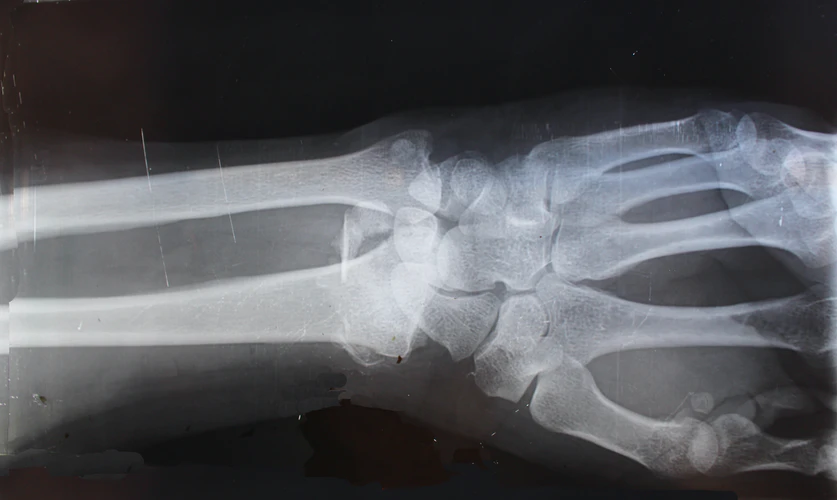

Остеопороз. Кости.

Остеопороз - это заболевание, которое характеризуется снижением плотности костей, в связи с потерей костной ткани. Так, кости становятся менее прочными и более склонными к травмам и переломам.

Таким повреждениям наиболее подвержены бедро, бедренная кость, плечевая кость, запястье и позвонки. Они происходят не спонтанно, а связаны с легкими ушибами или падениями, при которых здоровая крепкая кость не сломалась бы. Так, боль от остеопороза возникает именно из-за этой травмы, а не до неё. Существуют также переломы, которые остаются незамеченными из-за отсутствия боли или каких-либо симптомов, видны они становятся только при обследовании.